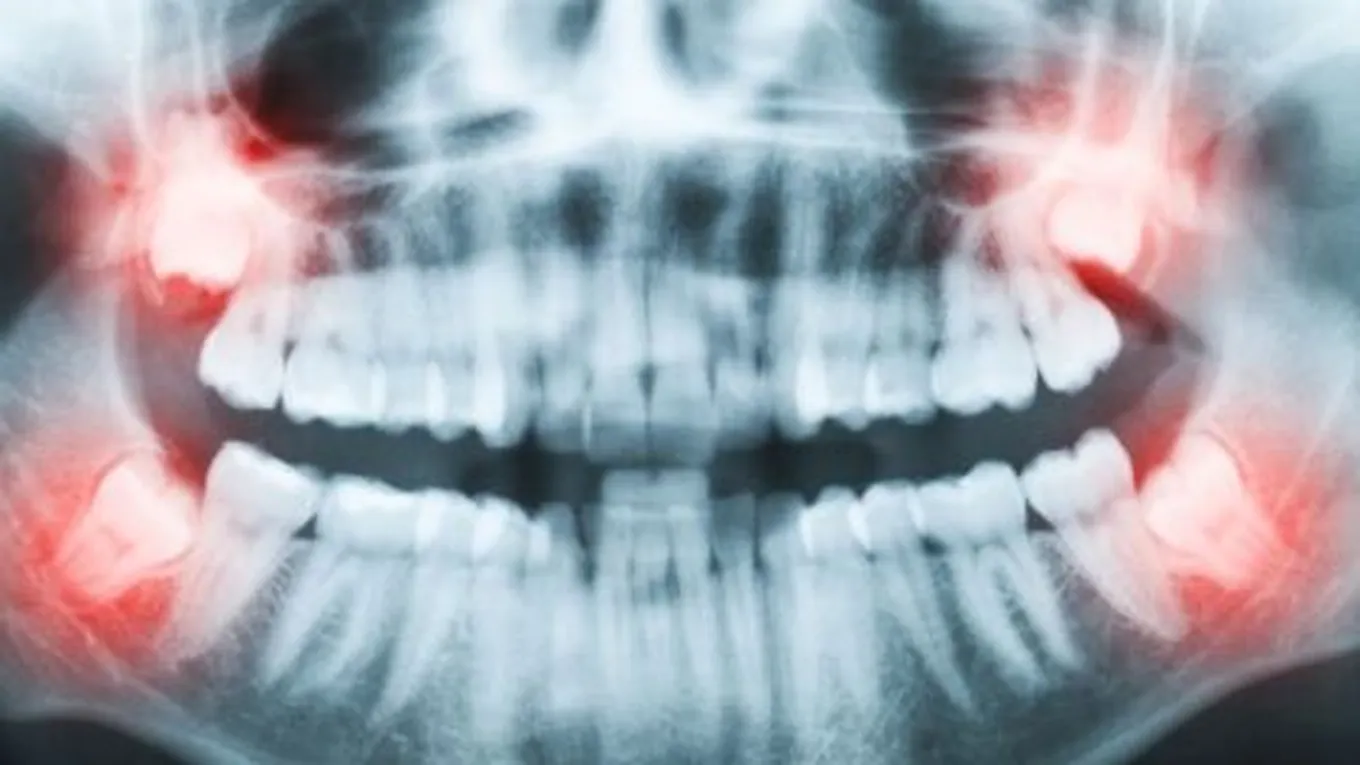

تعرف طواحين العقل بأنّها آخر ما ينمو من الأسنان، لكن لا يكون لديها مساحة كافية للنمو أو الخروج بشكل طبيعي؛ لأنّها توجد أقصى الخلف من الفم، ولمعظم الأشخاص أربعة طواحين عقل اثنتان في الجزء الخلفي من الفم واثنتان في الجزء العلوي منه، لكن من الممكن أن يكون لدى الإنسان عدد أقل أو أكثر من هذه الطواحين، وفي حالة زيادة عددها فإنّها تُسمى بالأسنان الزائدة، ويبدأ ظهورها في فترة العمر بين 17 سنة إلى 25 سنة.

إنّ المشكلة الأساسية في طواحين العقل أنّ كبر حجمها يؤثر في نمو بقية الأسنان الأخرى، كما أنّ ظهورها بشكل غير طبيعي كأن تنمو بشكل أفقي أو مائل يسبب التهابات شديدة في لثة الإنسان والأسنان المجاورة لها، كما يُمكن أن تنتفخ اللثة ويشعر الإنسان بألم شديد وغير محتمل عن نمو ضرس العقل تحت اللثة.